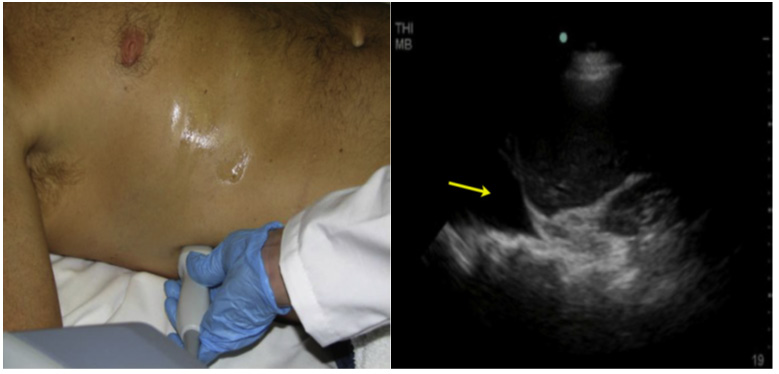

Subxiphoid or subcostal position

The transducer is located below the xiphoid process, almost parallel to the abdominal wall to observe the content of the mediastinum through the left hepatic lobe. The transducer needs to be angled slightly to the patient's left. In this position, the fluid in the pericardial sac around the heart can be clearly seen as a hypoechoic ring (Figure 7).

Figure 7 Subxiphoid window: sectoral transducer, in the lower portion of the xiphoid process, directing towards the patient’s left shoulder.

The effect of fluid on the right ventricle can be seen, although temporal resolution is slow, unless an echocardiographic transducer is used, signs of ventricular compromise can confirm a clinical diagnosis of cardiac tamponade (Figure 7A).

Figure 7A Anechoic image (*) that occupies the pericardium is evidenced, in a patient with closed chest trauma.

More recently, ultrasound has also been shown to be useful in diagnosing pericardial effusions in trauma patients.

The main reason for diagnosing pericardial effusions is to prevent trauma-induced patients from developing pericardial tamponade.

We incorporate the subcostal view of the heart as a part of the rapid examination in all patients with blunt abdominal trauma. This is useful in diagnosing pericardial effusions (Figure 7A).